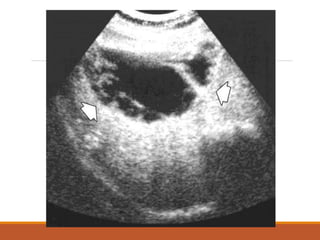

IMAGENOLOGÍA

USG Abdominal:

• Detecta lesiones mayores de 1 cm

hasta en el 90% de los casos.

•Bajo costo y sirve como guía en la

punción - aspiración de los mismos.

•Desventajas:

- No visualiza el domo del lóbulo hepático

derecho

- No detecta abscesos microscópicos

múltiples, tampoco abscesos pequeños

en hígado graso.

- Es operador dependiente.

El ultrasonido hepático es el procedimiento

inicial de elección y el más económico;

cuenta con la mayor utilidad global, pues,

además de poder diagnosticar o descartar

enfermedad biliar asociada, es capaz de

detectar casi 100% de los AHA, aunque

puede fallar en la detección de algunos

abscesos del lóbulo derecho.

El aspecto habitual de estas lesiones es una

imagen hipoecoica,

redonda u oval, sin ecos de pared.